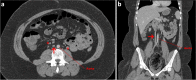

Patients with venous anomalies are at increased risk of developing venous thromboembolism (VTE) and subsequent complications, but they are often under-recognised. While unprovoked VTE may trigger testing for inherited thrombophilias and malignancy screening, anatomic variants are considered less often. Venous anomalies increase the risk due to venous flow disturbance, resulting in hypertension, reduced flow velocity and turbulence. Recognition is important as endovascular or surgical intervention may be appropriate, these patients have a high rate of VTE recurrence if anticoagulation is ceased, and the anomalies can predispose to extensive VTE and severe post-thrombotic syndrome (PTS). In this case series, we present representative cases and radiological images of May-Thurner syndrome (MTS), inferior vena cava (IVC) variants and venous aneurysms, and review the available literature regarding optimal diagnosis and management in each condition.